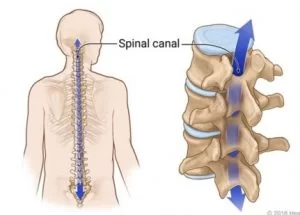

Τι είναι ο σπονδυλικός σωλήνας;

Ο σπονδυλικός σωλήνας είναι ένας σωλήνας, ένα “κανάλι” κατά κάποιον τρόπο, το οποίο σχηματίζεται από τη συνένωση των σπονδύλων. Μέσα στο σπονδυλικό σωλήνα υπάρχει εγκεφαλονωτιαίο υγρό και μέσα στο εγκεφαλονωτιαίο υγρό βρίσκεται ο νωτιαίος μυελός (στην αυχενική και θωρακική μοίρα) και τα νωτιαία νεύρα (Εικόνα 1).